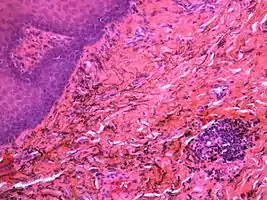

If necessary, the diagnosis can be confirmed histologically by excisional biopsy, which excludes nevi and melanomas.[4]: 138 If a biopsy is taken, the histopathologic appearance is:[1]

- Pigmented fragments of metal within connective tissue

- Staining of reticulin fibers with silver salts

- A scattered arrangement of large, dark, solid fragments or a fine, black or dark brown granules

- Large particles may be surrounded by chronically inflamed fibrous tissue

- Smaller particles surrounded by more significant inflammation, which may be granulomatous or a mixture of lymphocytes and plasma cells

Silver sulfide deposits are found in proximity to small vessels in the oral mucosa

Silver sulfide deposits in the surrounding area of skeletal muscle fibers of the oral mucosa